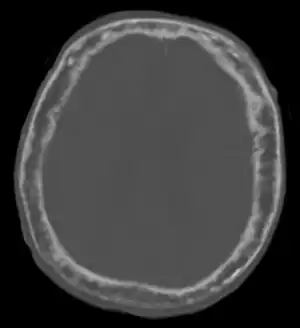

"This 92 year-old male patient presented for assessment of sudden inability to move half his body. An incidental finding was marked thickening of the calvarium. The diploic space is widened and there are ill-defined sclerotic and lucent areas throughout. The cortex is thickened and irregular. The findings probably correspond to the 'cotton wool spots' seen on plain films in the later stages of Paget’s disease."

Progressive effects of Paget's disease of bone in the head ("hyperostosis cranii")